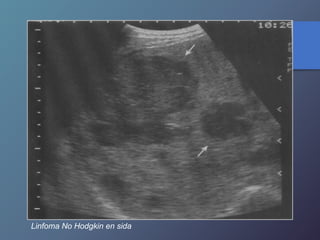

• Los linfomas hepáticos pueden manifestarse en masas

hipoecoicas, o difusas difíciles de diferenciar por ecografía

o TC.

Linfoma No Hodgkin en sida